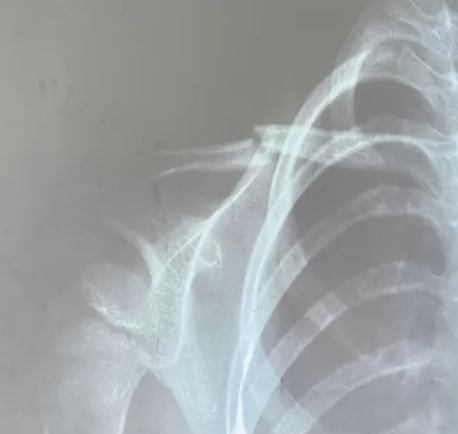

Clasificación de Allman para fracturas de clavícula.

A

Grupo I: tercio medio (más frecuente).

Grupo II: tercio distal.

Grupo III: tercio medial.

¿Qué porcentaje de fracturas del hombro corresponde a la clavícula?

50%.

Principales mecanismos de fractura de clavícula.

Caída sobre el hombro o traumatismo directo.